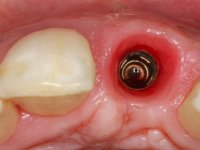

A full thickness mucoperiostal flap was performed, and horizontal and vertical bone loss became visible. A bone level implant was placed in the 21 area. The implant was placed in an optimal three-dimensional position – respecting the safe zone defined by the ITI Consensus with an adequate primary stability. However, this anatomically correct implant placement caused a buccal wall dehiscence. To treat this defect and also to correct the concavity observed in the alveolar bone crest, a simultaneous guided bone regeneration procedure was performed with a mixture of autogenous bone (collected from the osteotomy and harvested from the uppermost part of the buccal wall) and xenogenous bone. A collagen membrane was placed to stabilize the bone graft. The periosteum was released with horizontal incisions on the base of the flap to allow a tension-free repositioning over the submerged implant, and interrupted sutures were used.

After 12 weeks the restorative procedure was initiated with a first impression to prepare a screw retained lab restoration. A temporary abutment for bone level implant was used to create a proper emergence profile. Two months after the placement, the peri-implant soft-tissue configuration was considered adequate to allow the final impression. In order to satisfy the high esthetic demands of the patient, the fixed rehabilitation was made with zirconium oxide abutment and a press lithium disilicate glass-ceramic restoration.